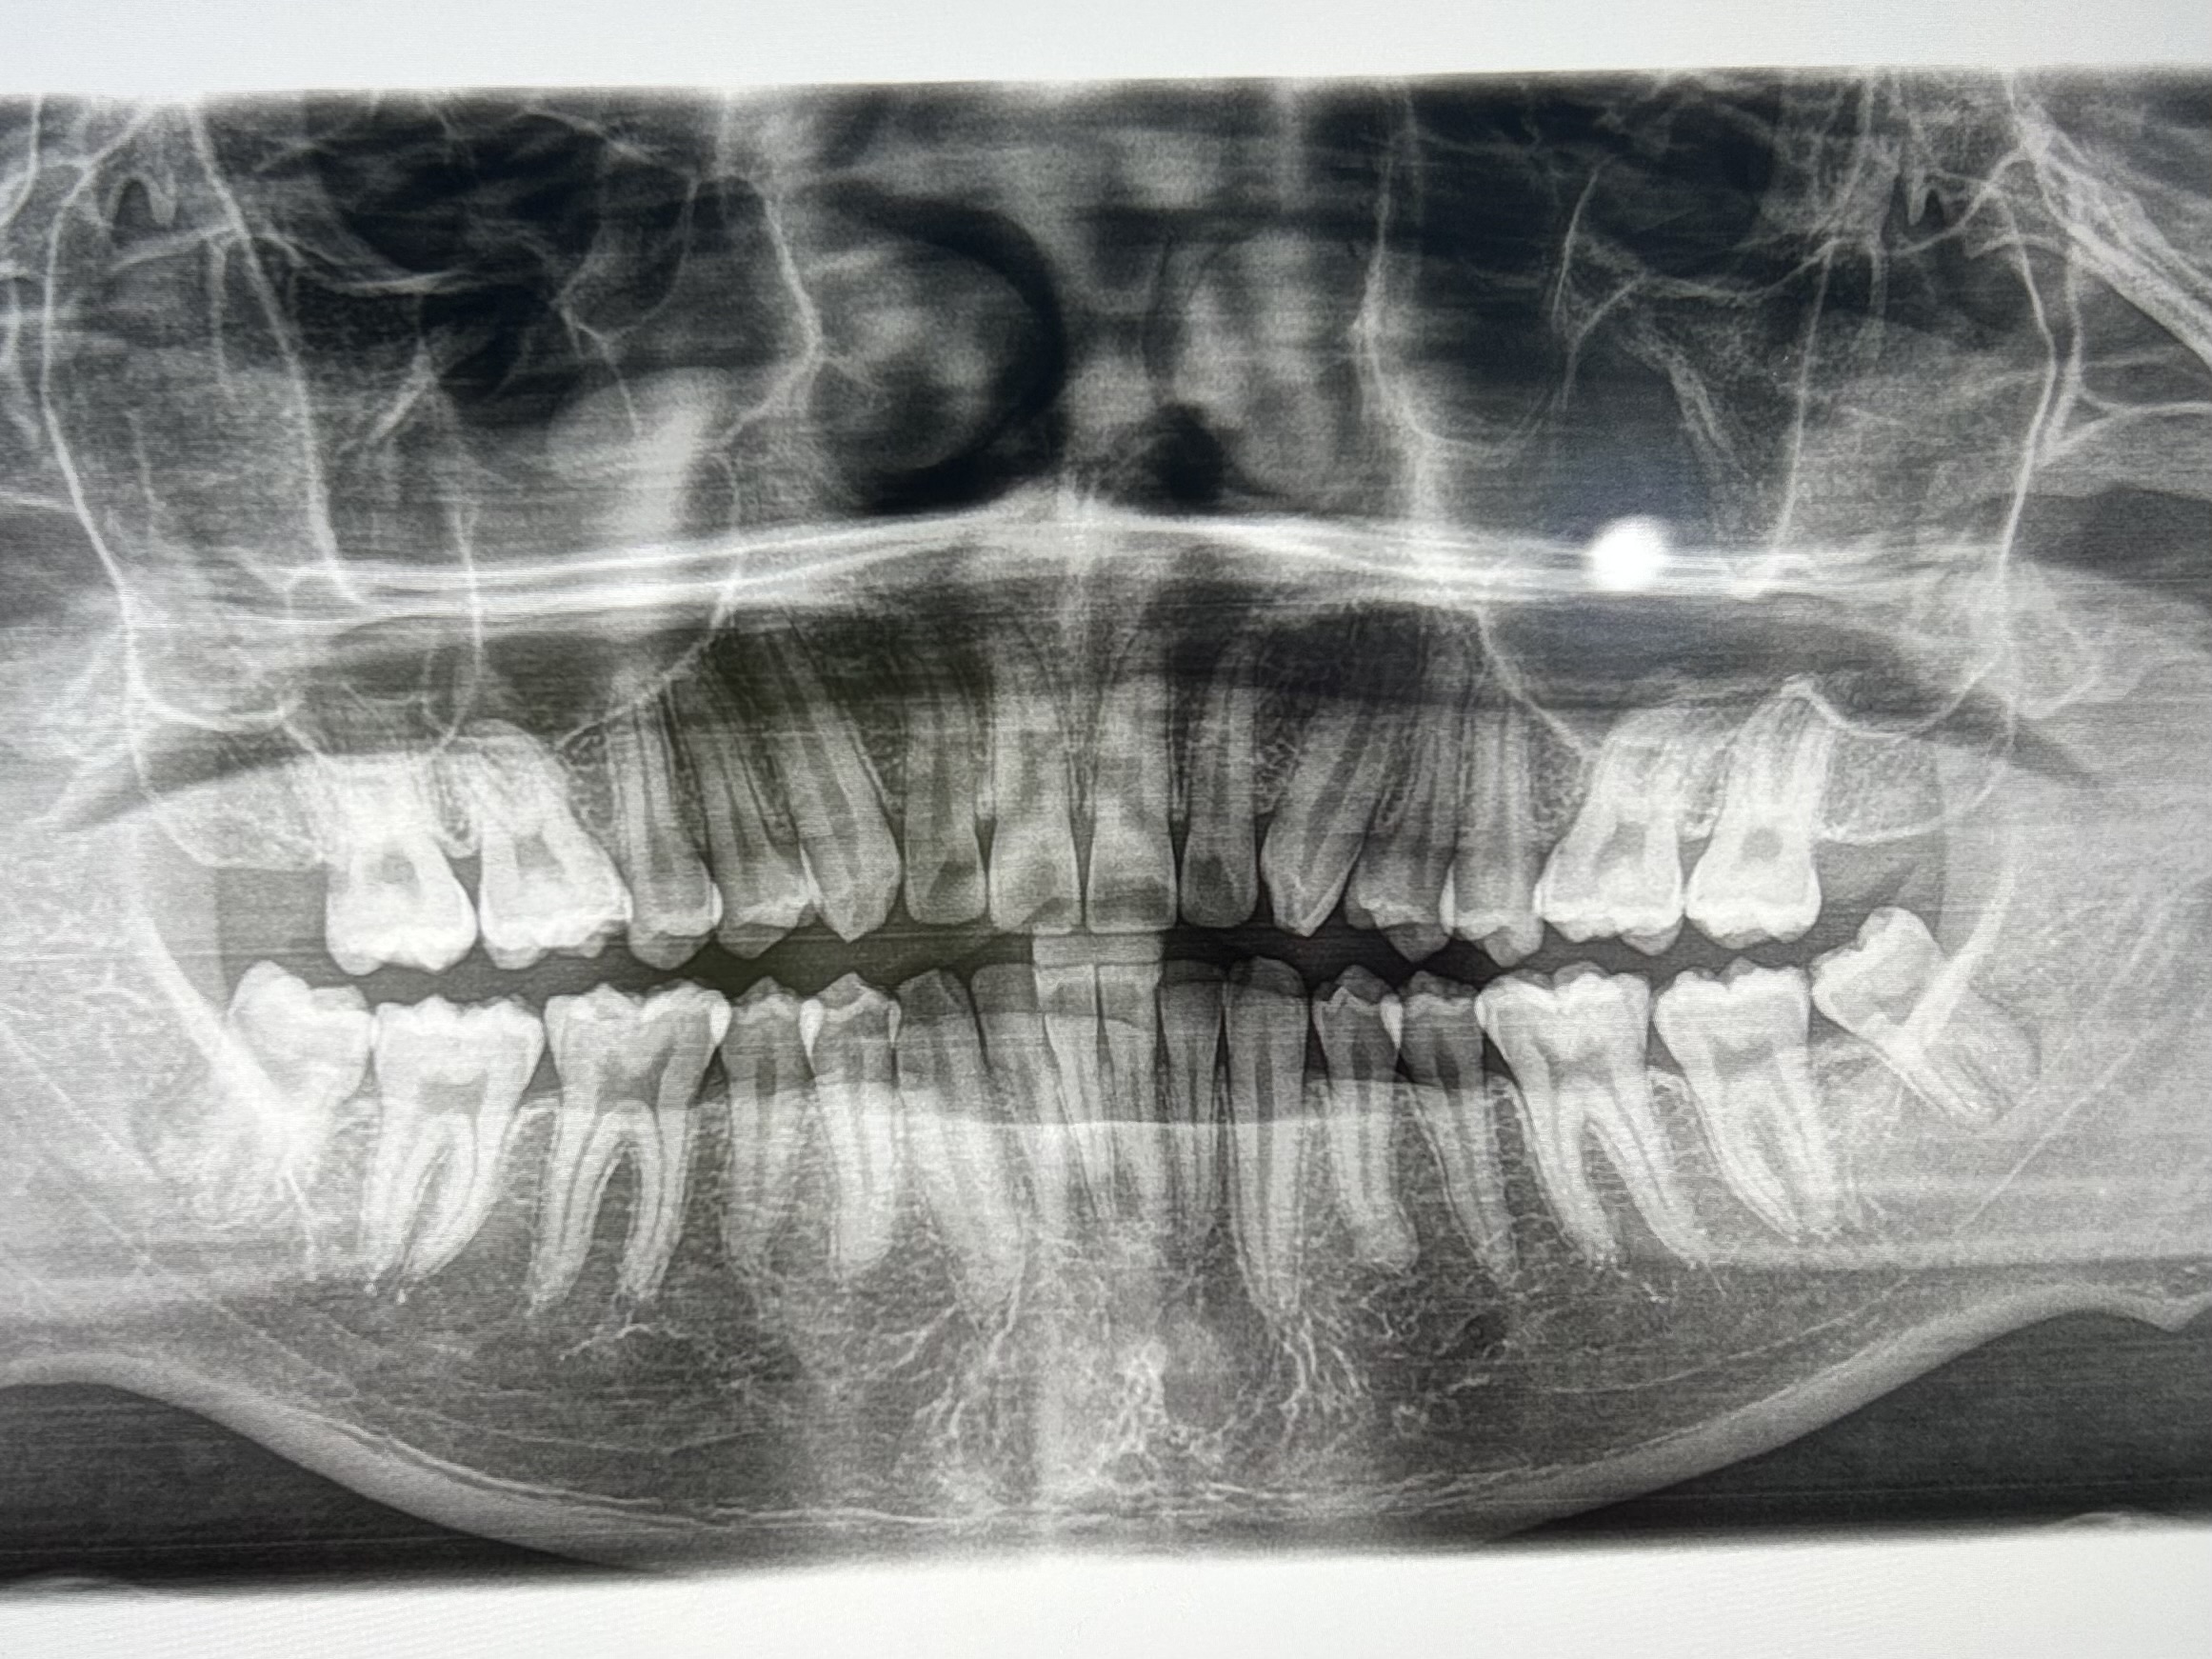

奥歯に向かって生えている親知らずはすぐに抜いた方がいいですか?

横向きで少しだけ生えている親知らずが痛みます。早めに抜くべきですか?

斜めに生えている親知らずの抜歯を勧められています。